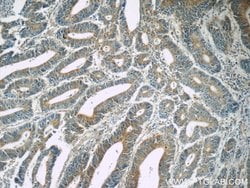

| Immunohistochemistry (Paraffin), Western Blot | |